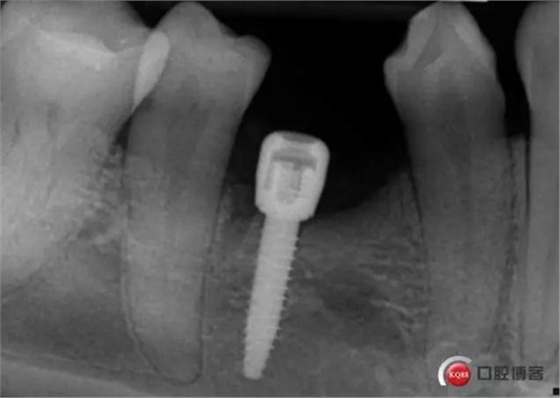

三個月后上基臺

3.jpg